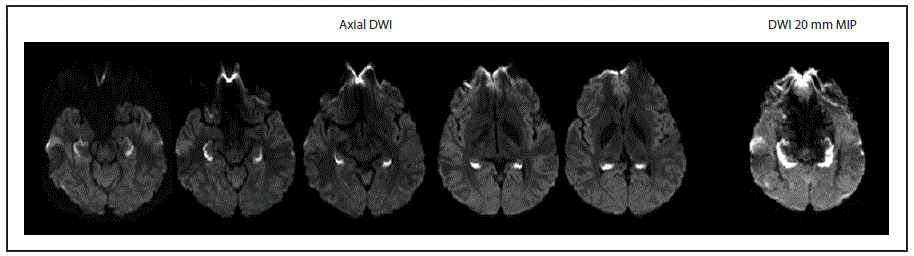

Return to your place in the textFIGURE. Diffusion-weighted imaging (DWI)* findings at initial brain MRI in a patient with unusual amnestic syndrome — Massachusetts, 2012

The figure above is a scan showing diffusion-weighted imaging findings at the initial brain magnetic resonance imaging of a patient with unusual amnestic syndrome in Massachusetts during 2012.

* Axial DWI demonstrates bright signal consistent with complete bilateral hippocampal ischemia. The complete extent of hippocampal ischemia is best evident on thick 20 mm MIP images constructed from the axial DWI data.